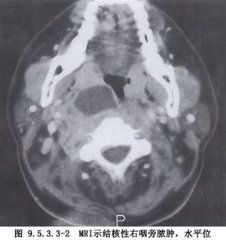

患側下頜下區腫脹,局部堅硬,觸痛明顯,病人頭部偏向患側以減輕疼痛。嚴重者腫脹範圍可上達腮腺,下沿胸鎖乳突肌而達鎖骨上窩。如已形成膿腫,則局部可能變軟。咽部檢查可見咽側壁隆起,軟齶及齶弓充血水腫,扁桃體被推向咽腔中央,而扁桃體本身無明顯病變,口腔內分泌物較多,因張口受限,有時咽部病變看不清楚。如為後隙感染,不引起牙關緊閉,扁桃體不被推移。

患側頸部頜下區及下頜角後腫脹,觸之堅硬、壓痛,嚴重者上達腮腺、下達胸鎖乳突肌及鎖骨上窩皆有腫脹。由於感染位於頸深部,故表面皮膚無充血,也觸不到波動感。咽側壁隆起並稍充血,扁桃體本身有或無病變並可被推向內側。必要時穿刺抽膿,即可確診。